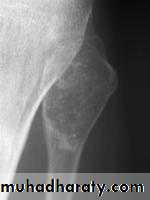

ChondrosarcomaSlowly growing

Primary or secondary to preexisting lesionC/F

Age 40 -50 yr

XR

Lytic lesion + flecks of calcification

Rx

Surgery

Radio- & chemoresistant

5 yr survival 60 %Objectives :